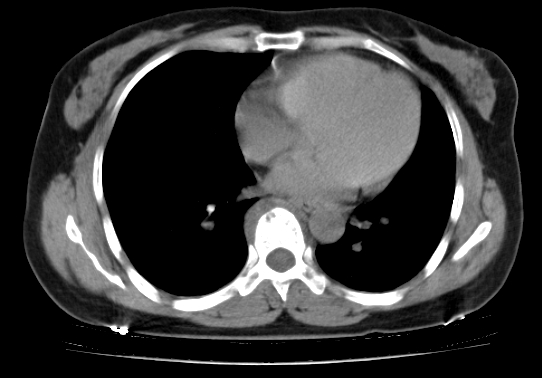

标题: CT25227:背部疼痛伴双侧胸壁痛2月,食欲差。 [打印本页]

标题: CT25227:背部疼痛伴双侧胸壁痛2月,食欲差。

肺结核并胸椎结核?请各位高手指教。

用椎体的条件来扫胸椎呀!考虑1左侧胸膜小结节形成2椎体结核并冷脓肿形成

考虑胸椎结核并椎旁软组织肿胀。

左肺结核灶,胸椎结核并冷脓肿。

左肺结核灶,胸椎结核并冷脓肿

食道癌并胸椎及肺内转移